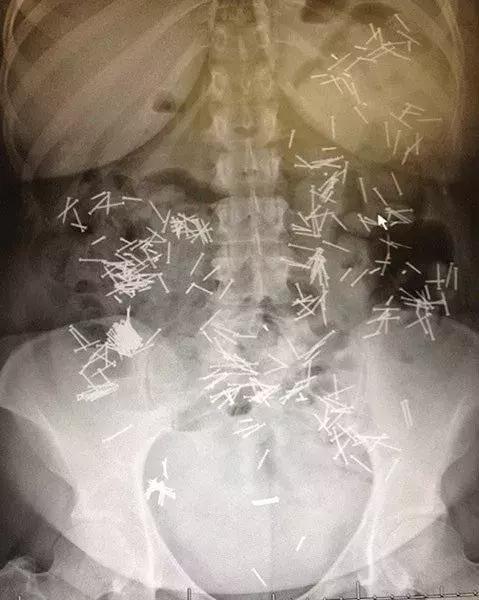

20.全都是钉子,不过居然都没有刺伤内脏

一些奇怪的X光照片,看完整个人都不好了……-20.jpg